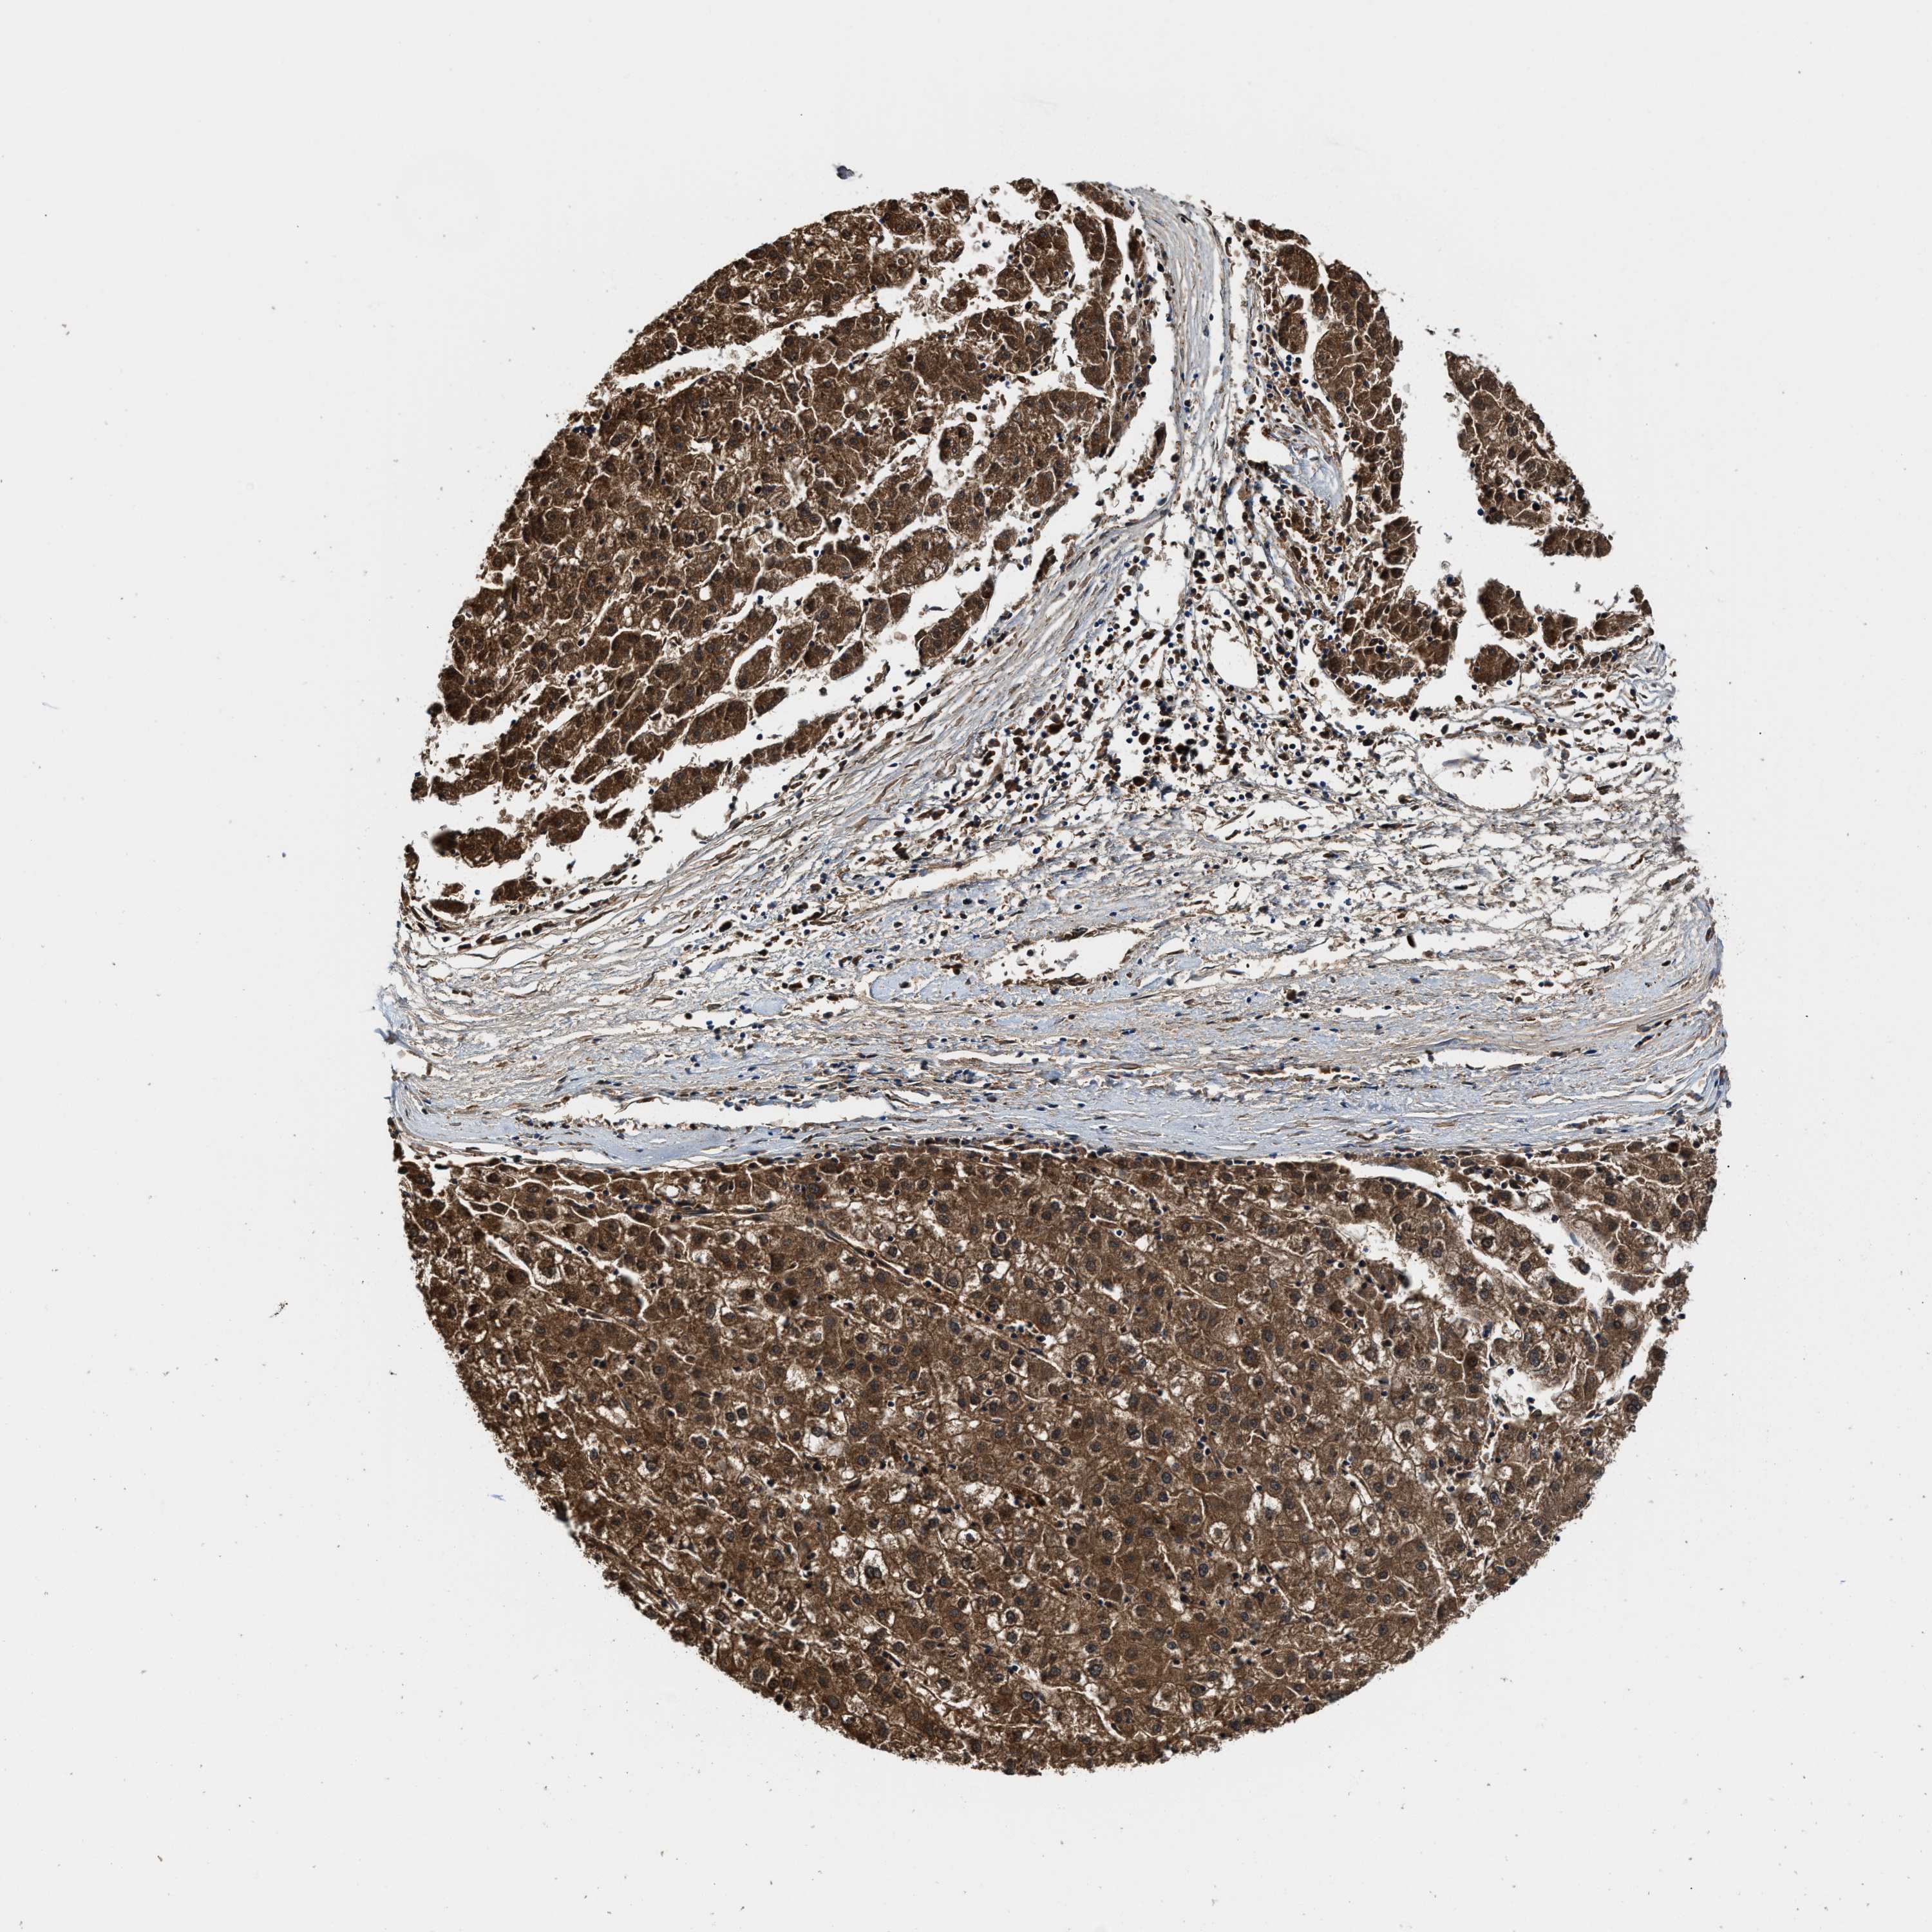

LIVER CANCER - Protein expressioni

A mouse-over function shows sample information and annotation data. Click on an image to view it in a full screen mode. Samples can be filtered based on level of antibody staining by selecting one or several of the following categories: high, medium, low and not detected. The assay and annotation is described here.

Note that samples used for immunohistochemistry by the Human Protein Atlas do not correspond to samples in the TCGA dataset.

Antibody stainingi

Antibody staining in the annotated cell types in the current human tissue is reported as not detected, low, medium, or high, based on conventional immunohistochemistry profiling in selected tissues. This score is based on the combination of the staining intensity and fraction of stained cells.

Each image is clickable and will lead to virtual microscopy that enables deeper exploration of all samples and also displays staining intensity scores, fraction scores and subcellular localization as well as patient and tissue information for each sample.

Antibody HPA008399

Antibody HPA017017

Antibody CAB015221

Staining

High

Medium

Low

Not detected

Intensity

Strong

Moderate

Weak

Negative

Quantity

>75%

75%-25%

<25%

None

Location

Nuclear

Cytoplasmic/membranous

Cytoplasmic/membranous,nuclear

Cholangiocarcinoma

Carcinoma, Hepatocellular, NOS